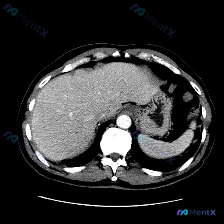

看到一张提示“脾脏病变(Splenic lesion)”的腹部MRI图像,整理了一下完整思路,这个病例其实挺典型的——很容易被预设带偏。 先看影像核心信息 这是一张腹部横断面MRI,从信号特征看(胃腔内高信号内容物、腹主动脉流空低信号),更像是压脂后的T2加权像(T2WI),而非标准T1加权像。 关...

看到一份挺有意思的资料,是关于“脾脏病变”的读片,但看完影像分析后发现情况和预设不太一样,整理一下思路和大家分享。 病例核心影像信息 这是一份单幅腹部CT横断面软组织窗图像的分析: 1. 各实质脏器表现: - 肝脏:密度均匀,边缘光滑,无局灶性占位,肝门部结构清晰,无血管或胆管扩张。 - 脾脏:形态...

今天整理了一个很有意思的「反向思维病例,不是教大家怎么「找病」,而是教大家怎么「信没病」。 --- 先看基本情况 预设疑问: 图像中观察到的具体异常是什么?脾脏病变 影像资料: 单张腹部增强CT(轴位软组织窗)+ 正式影像分析报告 --- 关键影像所见(严格基于报告) 这份正式影像分析是这么说的:...